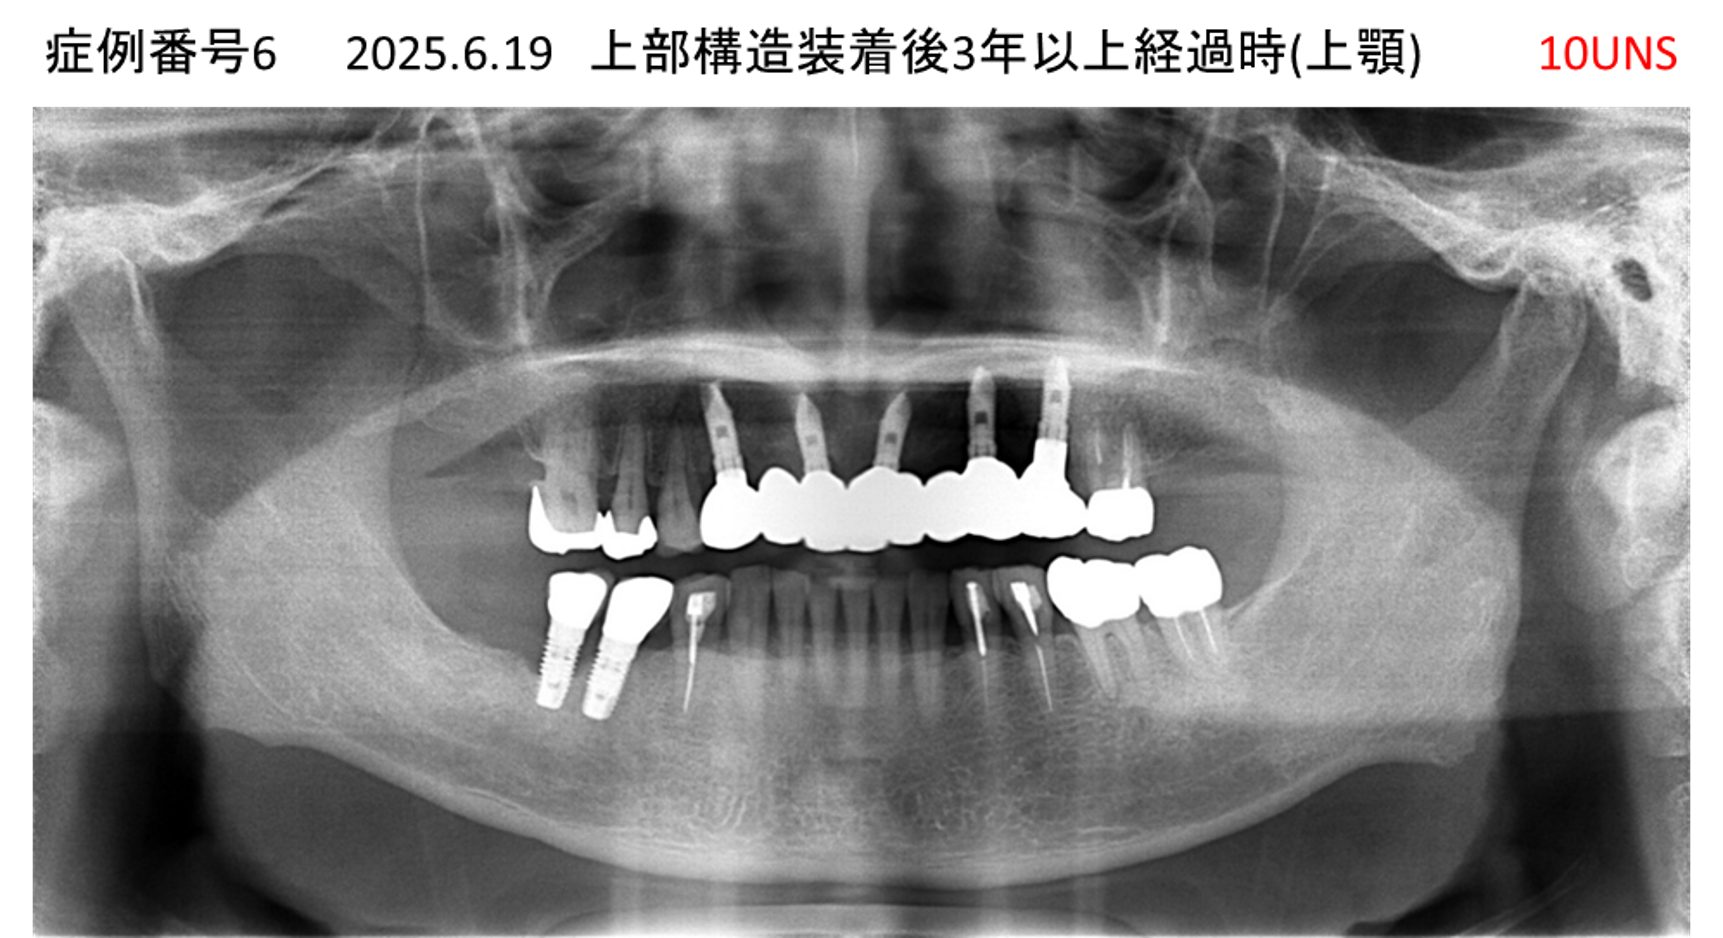

全く噛めない患者様のインプラント症例

| 治療名称 |

インプラントAGC |

| 治療費用 |

860万円+税 |

| 治療期間 |

12か月 |

| 患者さんの症状(主訴) |

全く噛めない、ごはんが後もに食べられるようになりたい、人前で口元を隠したくない |

| 治療内容 |

サイナスリフト、GBR、インプラント、AGC |

| 治療結果 |

しっかり噛めて踏ん張ることができる。食べ物をを選ばなくて済む、何でも食べられる、体重が増えた。見栄えがきれいすぎて自分じゃないみたい |

| 治療の注意点(リスク/副作用) |

インプラントが壊れたら再治療が必要 |